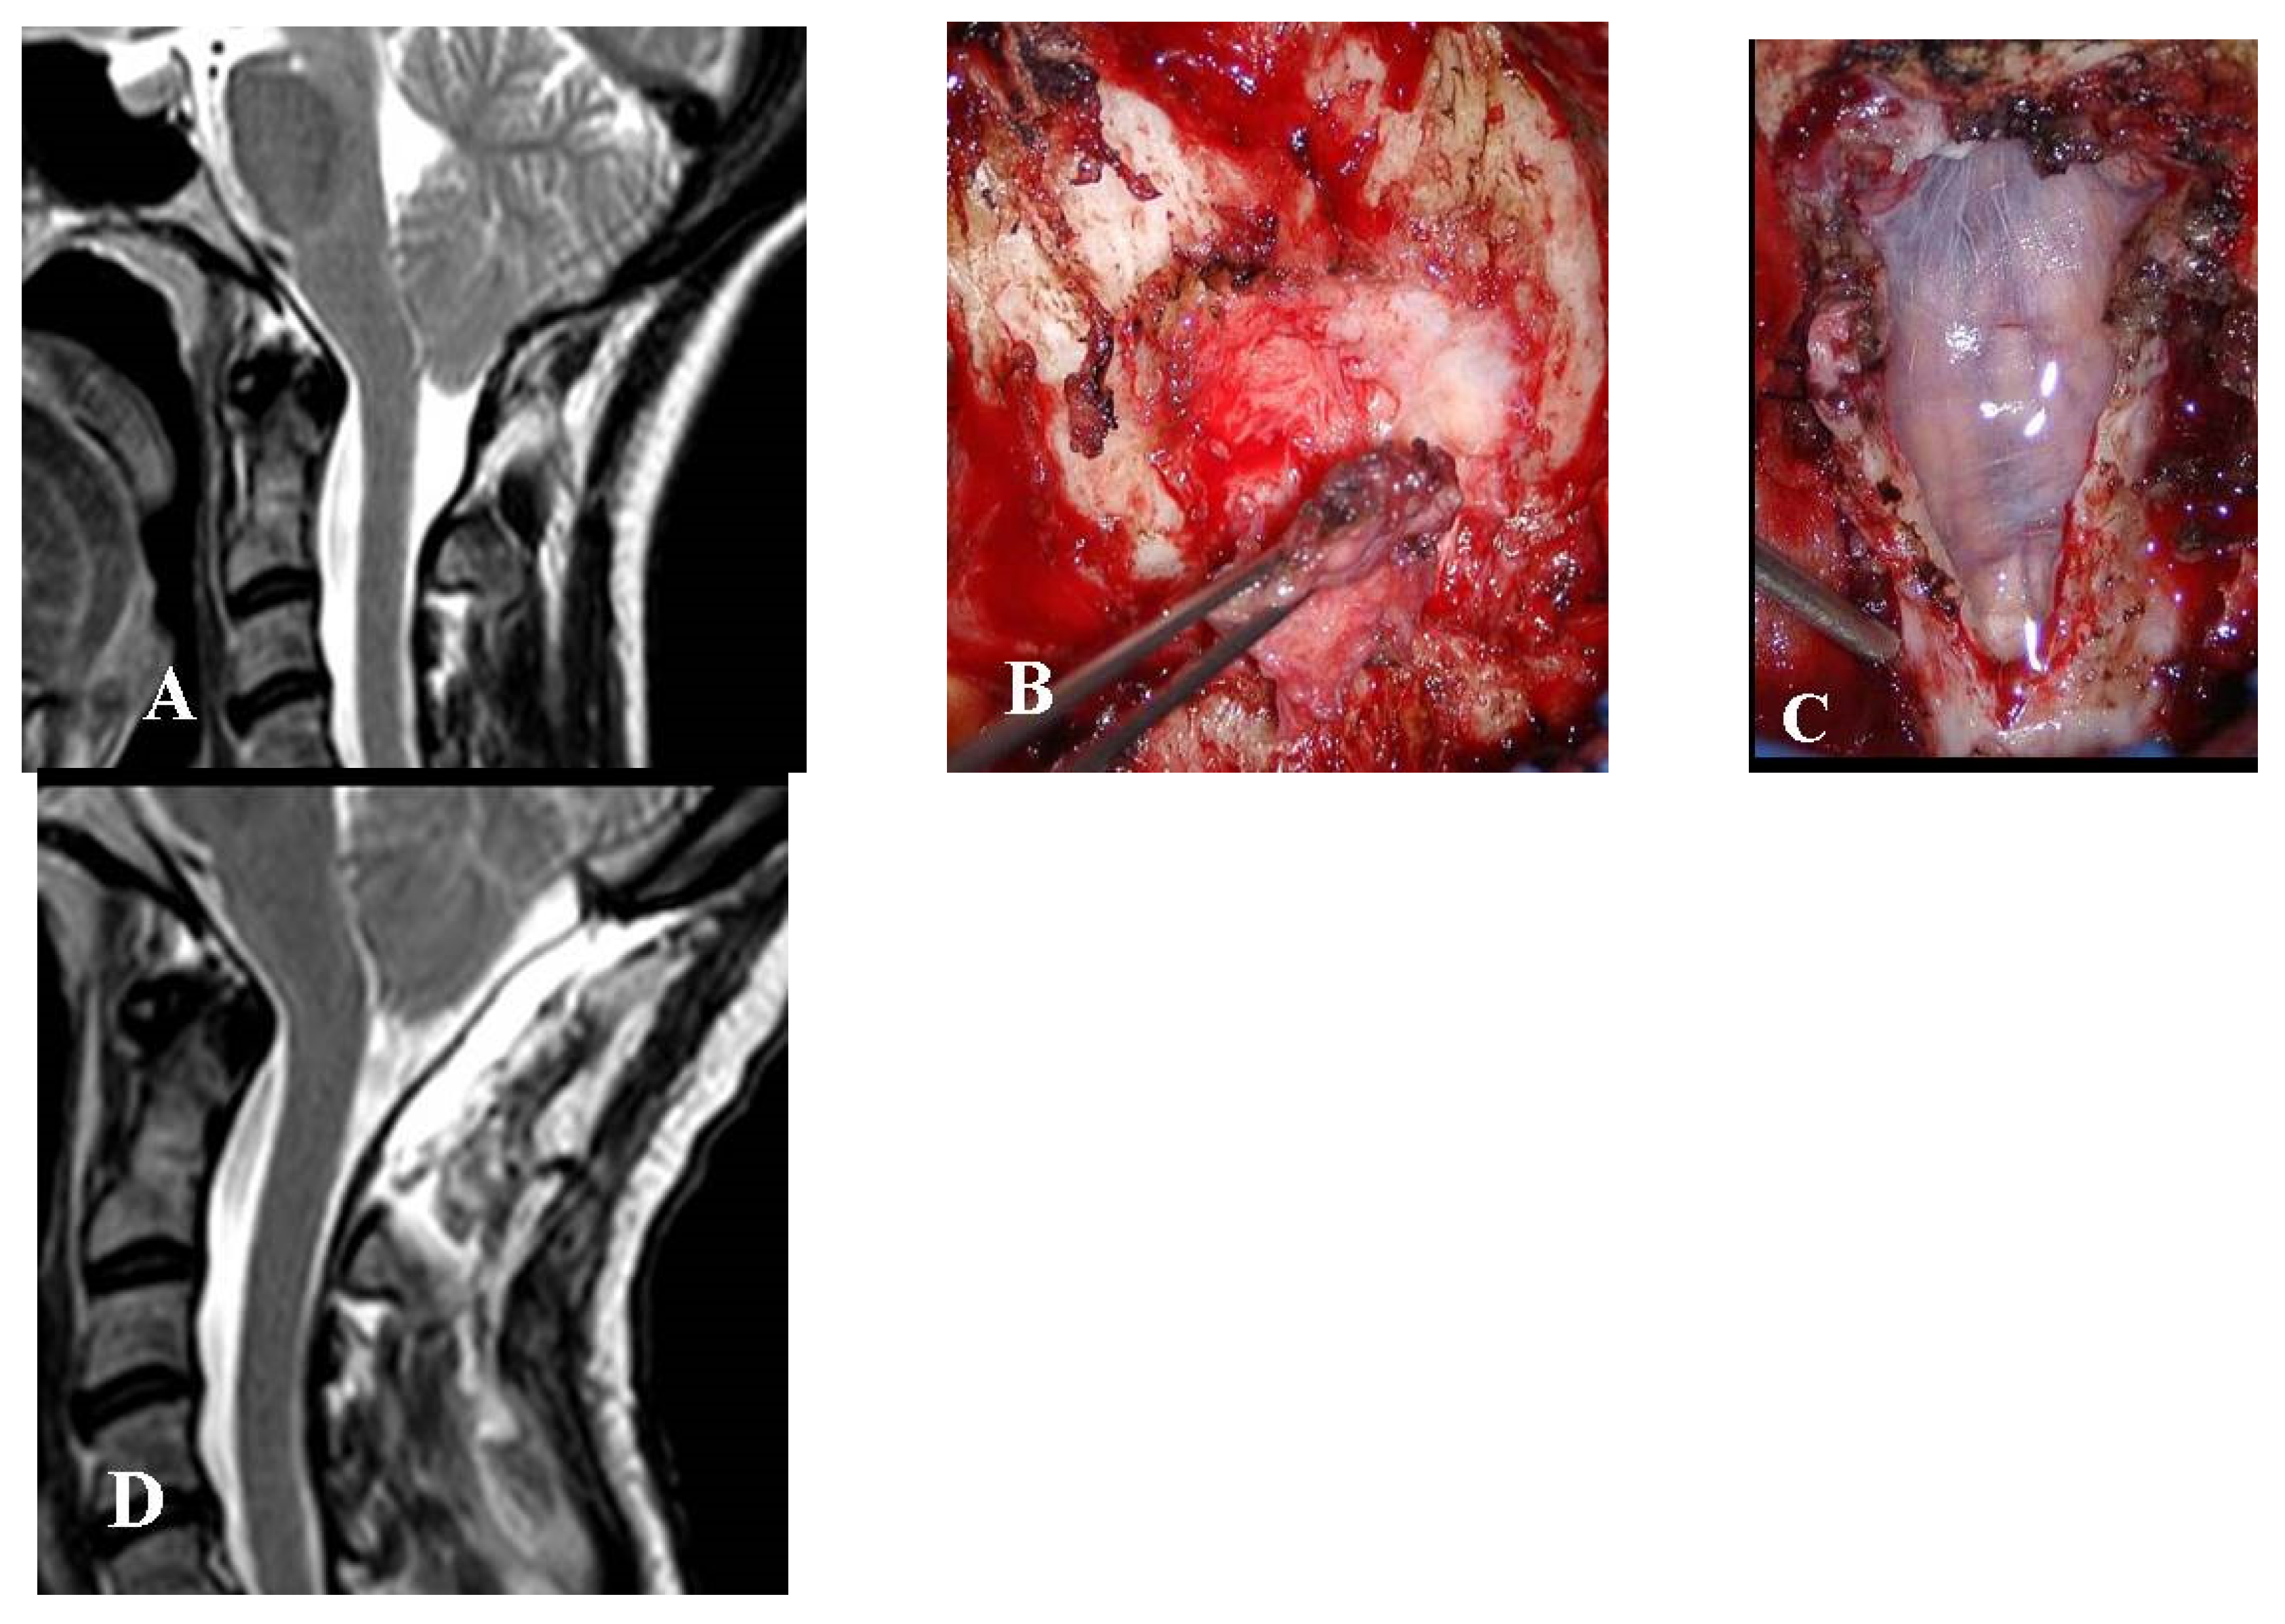

This group consisted of six adults and one boy (14 years of age) who received limited or no benefit from FMD. All of these patients were re-admitted 6 months to 8 years after surgery. One of these patients had even undergone EDS-FT (at another center), six months after the failed FMD. All of these patients complained of the persistence or recurrence of their preoperative symptoms (headache in all cases, impaired left hand in one case). Four patients, three adults, and one boy (14-year-old), with FMD-WDA underwent reoperation for dural sac augmentation (Figure 3).

All four patients with previous FMD-WDA improved following reoperation with dural augmentation (CCOS 14 in one case and 13 in three cases). As well as an extradural thick scar, fibrous extra-arachnoid bands were also found underneath the dural layer in all these patients. The subarachnoid space looked constricted and tended to expand as soon as the intradural bands were incised.

Figure 3. This 41-year-old woman had undergone bone decompression alone. Over the next 8 years, her headache recurred and progressively worsened. She also complained of dizziness and bouts of diplopia. (A) Preoperative MRI, T2-weight, sagittal view showing the bone decompression with scarce CSF film around the CM-1. (B) Intraoperative picture showing a thick and hard extradural fibrous scar that was maintaining the compression. (C) Intraoperative picture following dural opening with intact arachnoid. The dural sac was repaired using biologic graft. (D) Follow-up MRI, T2-weight, sagittal view obtained 6 months later showing the CM-1 was well bathed in CSF. Preoperative symptoms were almost completely resolved. The final CCOS score was 14.